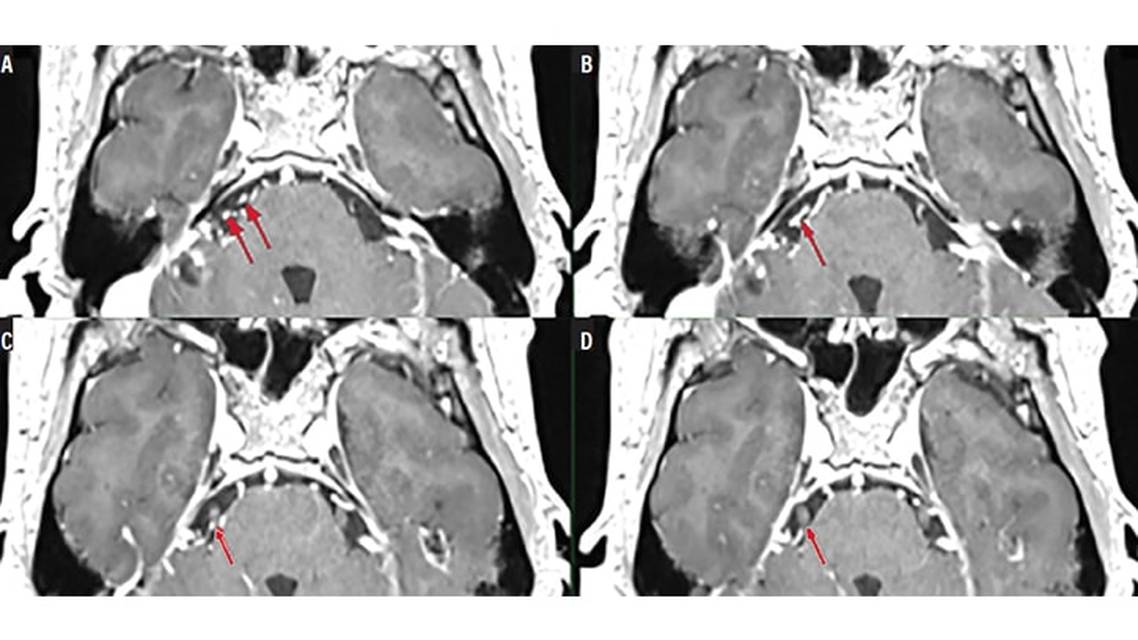

Mr. F had a brain MRI that showed a posterior fossa arteriovenous malformation (AVM). He was subsequently referred to neurosurgery. CT angiography showed a loop of anterior inferior cerebellar artery (AICA) likely to be compressing the trigeminal nerve (Figure 1). Diagnostic cerebral angiography was performed for characterization of the AVM demonstrated on MRI and CT angiography.

Diagnostic cerebral angiography confirmed the presence of a Spetzler-Martin grade II 2-cm AVM1 supplied by branches of the AICA and posterior inferior cerebellar artery (PICA) with both superficial and deep venous drainage (Figure 2).The trigeminal neuralgia symptoms were therefore thought to be associated with compression of the trigeminal nerve by an ectatic loop of AICA.

Mr. F elected treatment with endovascular embolization of the arterial feeding vessels. Embolization of a distal branch of right AICA and PICA with ethylene-vinyl alcohol copolymer was performed and showed resolution of the opacification of the ectatic loop of the AICA (Figure 2). Immediate relief of facial pain occurred immediately after the procedure and Mr. F remained symptom free without medication. Although symptoms did not recur, Mr. F chose to undergo definitive management via a second embolization procedure followed by surgical resection 4 months later owing to the rupture risk inherent to AVMs.1 His trigeminal neuralgia symptoms have not recurred, and over approximately 2 years of follow-up care, there has been no need for pharmacologic management.